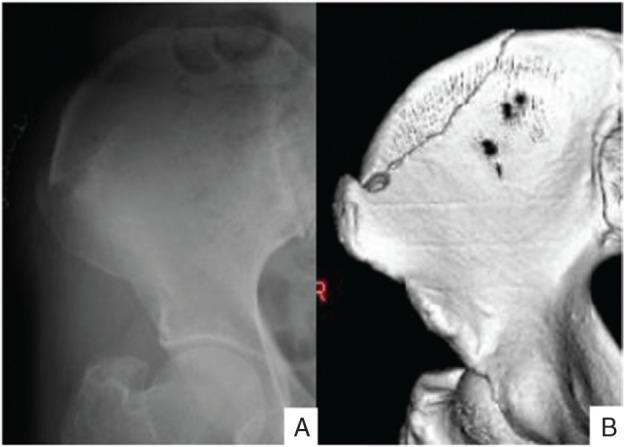

Although intervertebral implants have been advocated for cervical fixation surgery, classic Cloward's method or Smith-Robinson's methods using autologous iliac bone has been performed in our clinic for about 30 years. In most cases, the postoperative clinical course is uneventful with satisfactory result. However, the authors experienced three cases of donor site iliac bone fracture in the patients who performed anterior cervical fixation surgery. All three patients were female, elderly, short, and lean with low bone mineral density. Iliac bone fractures manifested with sudden pain in the vicinity of donor site. For the iliac bone fracture, two patients received invasive plate fixation surgery and the other was managed conservatively. As to the mechanism of donor site iliac bone fracture, the share stress during bone donation is speculated to cause iliac crest fragile. After beginning of walking after surgery, tractive force of the muscles attaching to the iliac crest play an important role in promoting the fracture cleft. Several clinical factors were analyzed to investigate the cause and prevention of this troublesome complication of cervical anterior fixation surgery. Age, female gender, lean, and small structure were risk factors for such iliac donor site fracture.

https://cdn.ncbi.nlm.nih.gov/pmc/blobs/3460/5364895/f3c794c952f3/nmccrj-2-109-g001.jpg